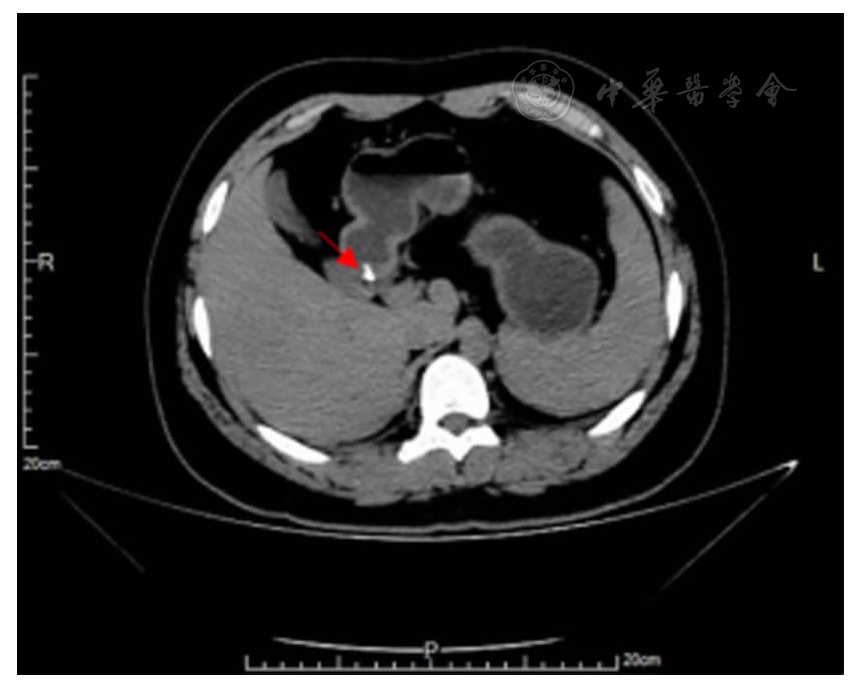

图1 腹部CT提示胃窦区胃壁及胃腔内V形高密度影